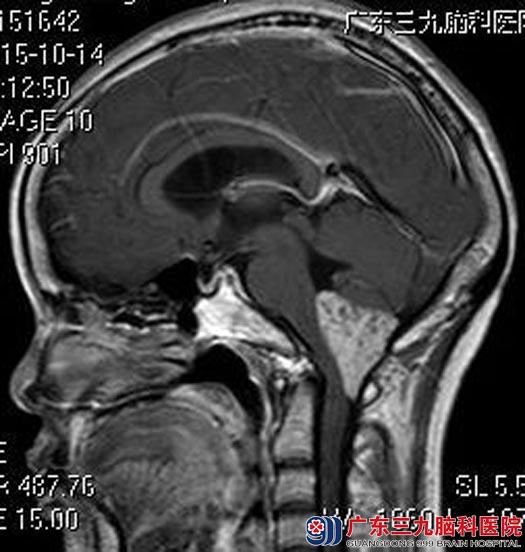

进一步头颅MR检查提示:四脑室下方及枕大孔区示一不规则团块状占位性病变,大小约4.5cm×2.8cm×3.0cm,病变向下突入枕大孔,脑干及小脑受压,考虑室管膜瘤可能。